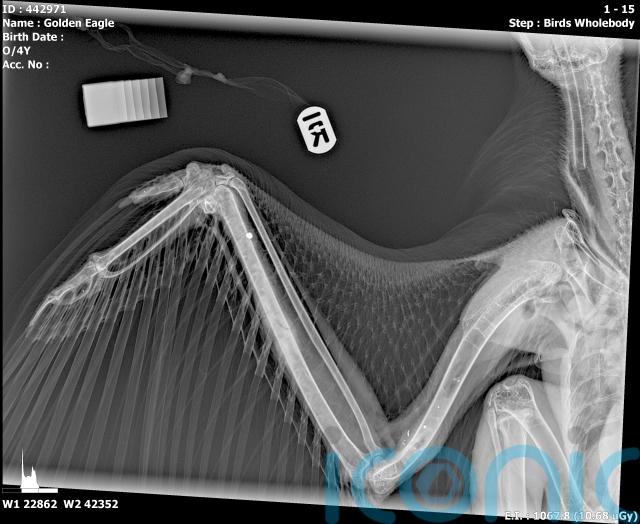

Police are investigating after a golden eagle was shot in the south of Scotland, with the rare bird making a full recovery despite being wounded by shotgun pellets to its wing.

Four-year-old Hamlet had been relocated to the Scottish Borders from the Outer Hebrides in 2023.

On January 20 this year, a gamekeeper in an estate near Stanhope discovered the injured raptor, which had a satellite tracking device.

A vet treated the golden eagle and it made a full recovery before being released back into the wild.

After reviewing the tracking data, police believe Hamlet was shot during the first week of January 2026 in an area between Stanhope and Glenbreck, off the A701 road.